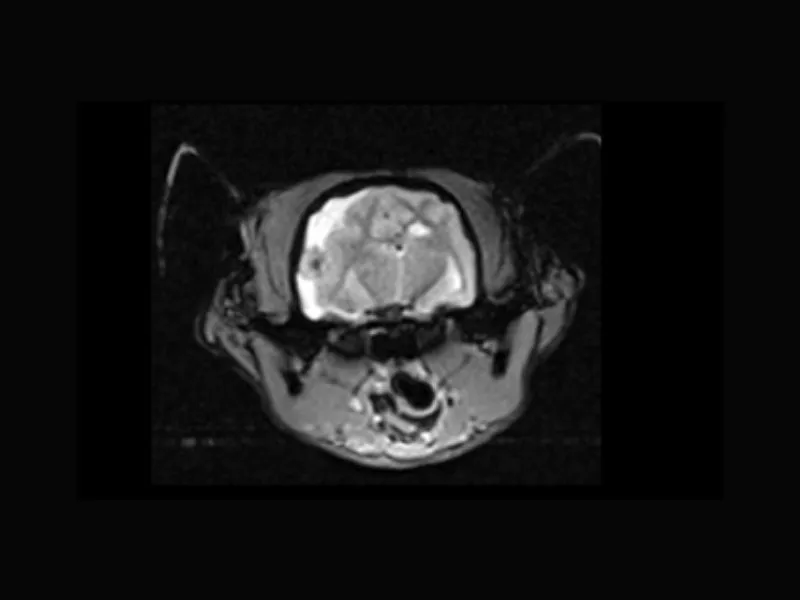

Magnifico Vet – SE T1 Transverse Neurocranium pre contrast

Magnifico Vet – SE T1 Transverse Neurocranium post contrast